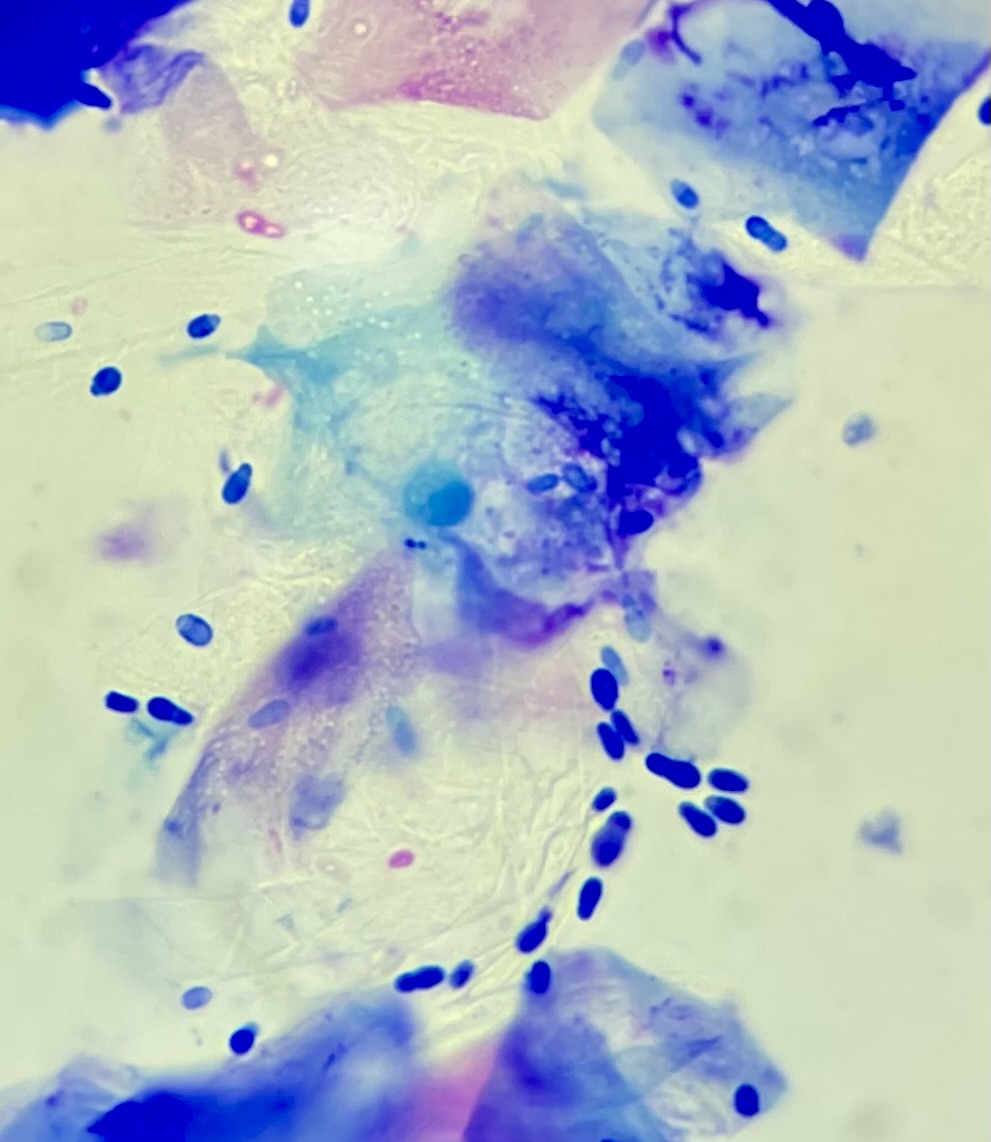

Dermatology – anal glands, ears, allergies

The number one presentation we see in first opinion small animal practice is canine allergic skin disease. This is by far the biggest problem we see in dogs, and to some degree cats. Allergies present in different ways, but common areas affected include ears, feet, and around the anal area. The key point to make is that allergies are long term and tend to escalate over time. Chronic untreated allergies can lead to permanent scarring and infection of the ears, and the constant itching makes dogs miserable, not forgetting the sleepless nights for their owners! At Whisker & Woof, we make an initial diagnosis fast and relieve your pet’s distress as quickly as possible. We then schedule a follow-up process over the coming months whereby we differentiate between food allergy and environmental allergy. We constantly refine and adjust the treatment plan so that ultimately your best friend is comfortable and happy, and you are empowered at home to understand and manage your pet’s condition. We also see a lot of chronic anal gland problems. Again, there is generally an underlying reason and simply expressing them every few months is not the long term solution. By taking care and digging a little deeper, we can often advise on why the problem is happening and can then start a management plan to control it.

Endoscopy

At Whisker & Woof, we have invested in rigid and flexible endoscopes that enable us to examine noses and bladders, through to the lungs and the digestive tract in both dogs and cats. We also have the training and experience to operate these sophisticated diagnostic tools, and use them purposefully to take samples and get to a diagnosis.